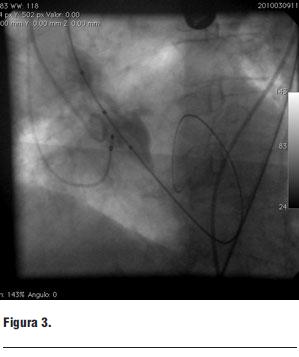

El nuevo ecocardiograma evidencia un área valvular aórtica de 0,32 cm2, un gradiente máximo de 92,4 mmHg y medio de 61,5 mmHg, con FEVI de 28%.

Se recalcula el riesgo quirúrgico, estimándose una mortalidad por Euroscore de 30,2% y por STS Score (Society of Thoracic Surgeons) de 26,5%.

1. Ecocardiograma transtorácico y transesofágico (figura 1 a y b)

- FEVI: 28%.

- Gradiente pico: 92,4 mmHg.

- Gradiente medio: 61,5 mmHg.

- Anillo aórtico: 23 mm.

- Diámetro de aorta a 40 mm del anillo: 32,8 mm.